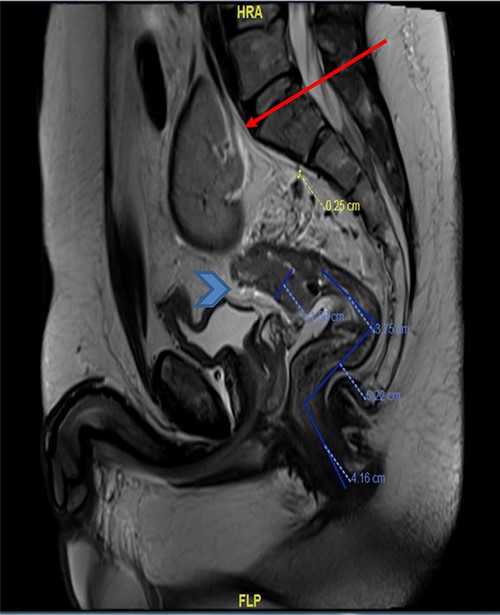

MRI pelvis (sagittal view) showed upper rectal mass with mesorectal fat involvement (arrowhead) and ectopic pelvic kidney (arrow).

The basic lab Investigation showed Hgb level of 8.6 g/dL and CEA level of 4.8 ng/ml. On further investigation, colonoscopy revealed a large friable fungating circumferential rectal mass at 9 cm from anal verge extending to the distal sigmoid colon, it was nonobstructing with a length of 8 cm and the rest of the colon was normal. A biopsy from the mass was taken and showed invasive moderately differentiated adenocarcinoma. On further routine of radiological staging, CT of the chest, abdomen and pelvis confirmed the upper rectal mass with ectopic malrotated left kidney located in the lower abdomen and upper pelvis, opposite to L5-S1 vertebral bodies (Figs 1 and 2). There was no peritoneal disease or distant metastasis. Moreover, MRI pelvis showed again an upper rectal mass with mesorectal fat invasion and multiple lymph nodes (T3N2) and confirmed an ectopic left kidney (Figs 3 and 4).